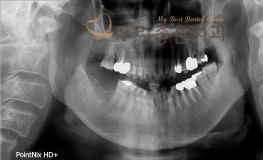

우리좋은치과 치아 상실로 인한 임플란트 보철 치료(김**2018.10.26~2019..

No.292

임플란트

2019-05-31

1571